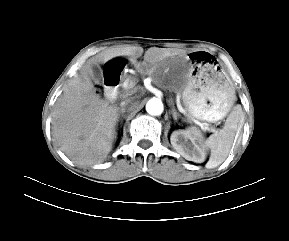

标题: CT19533:病变来源于哪?

患者,男,发现上腹部包块两月余。

病变位于肝胃间隙,实际就是位于小网膜囊(左肝下后间隙),呈轻度不均匀性强化,腹腔内及腹膜后见多发肿大淋巴结。所以我考虑肝胃间隙恶性胃肠间质瘤并淋巴结转移。

病灶强化不显著,灶周及腹膜后见多量淋巴结肿大,考虑淋巴瘤可能,其次考虑间质瘤

病灶与胰腺分界不清,来源于胰腺?

强化后病变与胃壁分界清楚,并且血供不是来源胃壁血管。考虑胰腺颈体癌并腹腔腹膜后淋巴结转移。

考虑胃肠间质瘤,病灶与胰腺分界不清,不除外胰腺肿瘤!